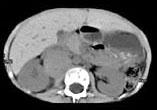

问题 男,5 岁,消瘦、贫血、纳差和腹部包块3个月,CT检查如图,下列说法正确的是 ( )

选项 A、该病灶来源于右肾上腺,考虑为神经母细胞瘤 B、该病灶来源于右肾,考虑为肾胚胎瘤 C、肿块密度不均匀,可见片状的较高密度,考虑为出血,也可见点状的钙化影 D、该病灶来源于肝脏,考虑为肝母细胞瘤 E、右侧腹腔内可见一巨大软组织肿块影,其边界欠清楚

答案 ACE